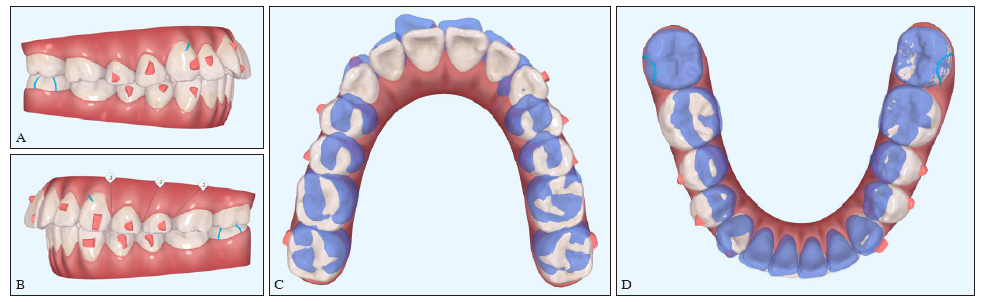

图 15

Clincheck 治疗方案A:Clincheck方案右侧观;B:左侧观;C:上颌面观;D:下颌面观。A、B:红色为附件,蓝色为精密切割的拉钩和磨牙挖开,便于橡皮圈牵引;C、D:蓝色为治疗前,白色为目标终末位。"